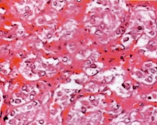

查看答案图所示肾上腺肿瘤首先应考虑的病理诊断是()

A、肾上腺醛固酮瘤

B、肾上腺皮质腺瘤

C、肾上腺嗜铬细胞瘤

D、肾上腺皮质癌

E、肾上腺皮质增生结节